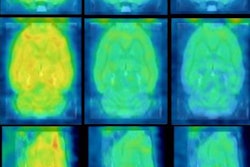

The researchers found that PET imaging visualized significant accumulation of both F-18 FDG and F-18 fluoromaltohexaose in the infected rats. No such accumulation was seen in the control rats, according to the group. In the rats with inflammation, significant accumulation was observed with F-18 FDG but not F-18 fluoromaltohexaose.